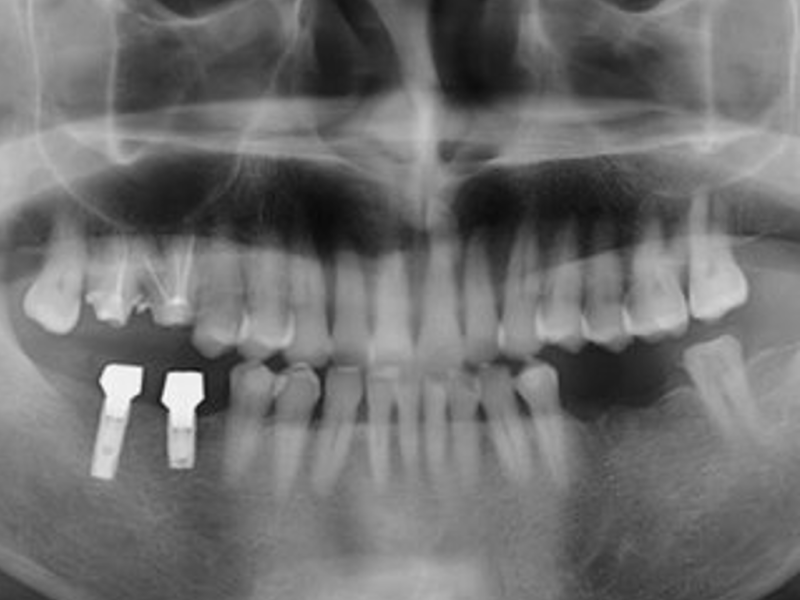

- 엑스레이나 CT 스캔을 사용하여 턱뼈와 주변 구조를 평가하고 임플란트 식립에 적합한 위치를 결정합니다.

Fixture가 턱뼈에 성공적으로 통합되었는지 확인합니다.